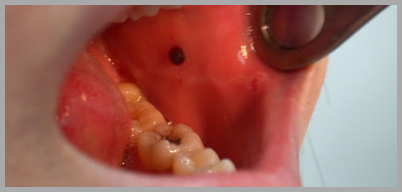

입안 피멍울 원인과 치료방법 관련 5가지 주의사항

안녕하세요. 수란건강연구소 소장 수란선생입니다. 오늘은 많은 분들이 호소하시는 질환인 입안 피멍울에 대해 살펴보겠습니다. 갑작스럽게 멍울이나 덩어리가 만져진다면 우리는 큰 걱정에 빠질 수 있습니다. 혹시 암은 아닐까 하는 걱정이지요. 여러분도 혹시 이러한 상황에 놓이셨나요? 그렇다면 집중하세요. 입안 피멍울의 원인과 치료, 그리고 관련한 중요한 내용에 대해 공유드리도록 하겠습니다. 아래의 내용을 잘 참고하셔서 소중한 여러분의 건강을 지키시기 바랍니다.

입안 피멍울 원인과 치료법에 대해 본격적으로 알아보기 전에 왜 입안 피멍울이 문제가 되는지 알아보도록 하겠습니다. 일반적으로 이러한 증상이 나타나는 경우는 몸의 면역력이 떨어졌을 때 입니다. 그런데 요즘과 같이 개인의 면역문제가 중요한 때에는 입안 피멍울 자체가 위험신호가 될수 있는 셈이지요. 그럼 아래에서 관련 내용에 대해 구체적으로 살펴보겠습니다. 자세한 정보가 궁금하시다면 아래를 참고하세요.